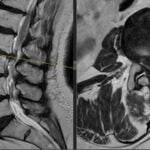

Infiltrațiile transforaminale sunt proceduri medicale minim invazive utilizate pentru diagnosticarea și tratamentul durerilor de spate și a altor afecțiuni legate de coloana vertebrală.

Aceste proceduri implică administrarea de medicamente, cum ar fi corticosteroizii și anestezicele, direct în spațiul în care se află nervii spinali, cunoscut sub numele de foramina.

- Leziuni ale nervilor sau vaselor de sânge: Procedura implică administrarea medicamentelor în apropierea nervilor spinali și vaselor de sânge, ceea ce poate duce la leziuni în cazul unei erori în efectuarea procedurii.